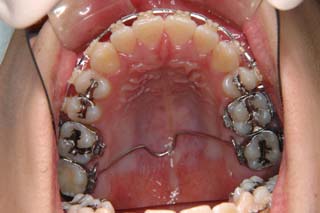

使用した主な装置名:TPB、マルチブラケット装置、オーソアンカー SMAPシステム

マルチブラケット装置でまっすぐに並べただけの状態です。なるほど、まるで噛めてない状態なのがよく分かります。ここでよく有りがちな矯正治療だと、上の前歯と下の前歯にゴムを1日中かけて噛ませていくのですが、それでは以前と同じく、関節をずらして噛むだけの人になってしまうでしょう。特に垂直的なコントロールが必要と考えられた上顎左側に オーソアンカー SMAPシステム の植立を行いました。